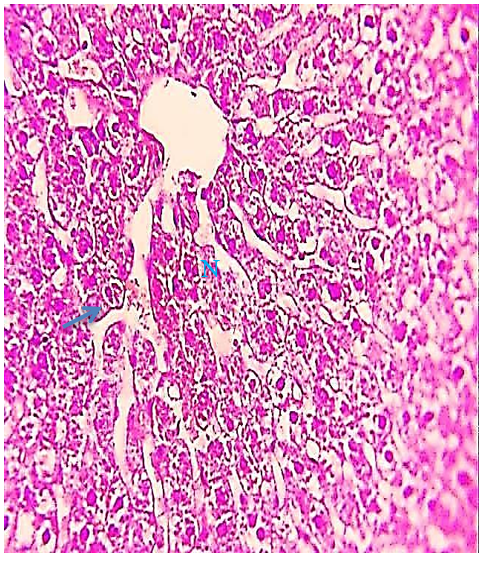

The 5.7 mg group on days 7 and 15 showed more acute histopathological differences compared to the other groups, including areas of hydropic degeneration, hypertrophied nuclei, marked complete distortion of the hepatic cell cords, loss of hepatocytes around the central vein, highly dilated sinusoid and highly congested hepatic portal vein, necrosis and damage of hepatocytes, acute congestion of the hepatic portal vein, loss of hepatocytes cytoplasm, loss of normal radial cords regulation of hepatocytes around the hepatic portal vein, hypertrophy of hepatocytes and aggregation Kupffer cells around portal vein (Figures 8-10), While the 5.7 mg group on day 30 showed marked complete distortion of the hepatic cell cords, large areas of hydropic degeneration, nodal inflammatory cell infiltration, acute cytoplasm vacoulation, prominent fragmented pyknotic nuclei, loss of hepatocytes nuclei, highly congested hepatic portal vein, hemolysis blood cells, increased proliferation in highly elongated wall of the bile duct, hypertrophied nuclei, congested blood sinusoids and numerous hemorrhagic areas, and edema (Figures 11-15).

Figure 12) Liver section of the 5.7 mg CBZ group on day 30 showed prominent fragmented pyknotic nuclei (arrows), increased proliferation in a highly elongated wall of the bile duct (circle), areas of hydropic degeneration (D), loss of hepatocytes nuclei (head arrow), and necrosis of hepatocytes (star) (H&E 400X)